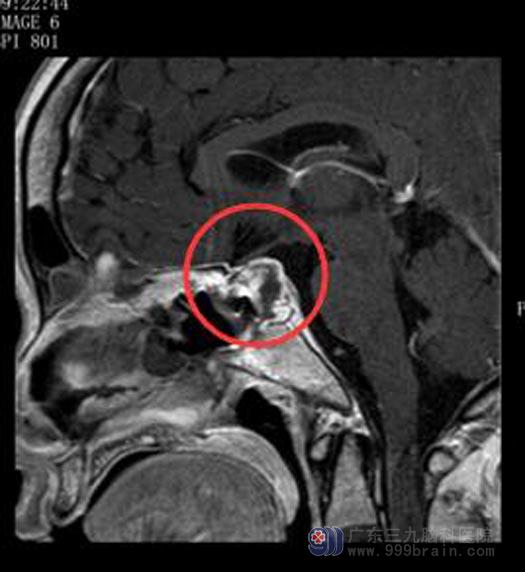

鲁明主任主刀在全麻下行“内镜经鼻蝶垂体瘤切除术+颅底重建术”,导航定位暴露蝶窦开口,全层切开硬脑膜,肿瘤组织质地软,易刮出,手术顺利。手术后谭女士视力、视野、尿量等都很正常,生命体征平稳。

手术后